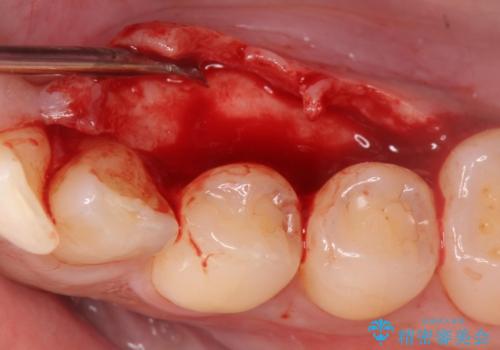

- 下顎の骨隆起を取りたいとのことで来院された患者様です。

一般的な歯科治療で用いる局所麻酔下で進めていきます。

右側と左側で2回に分けて行いました。

術後1週間での抜糸となります。